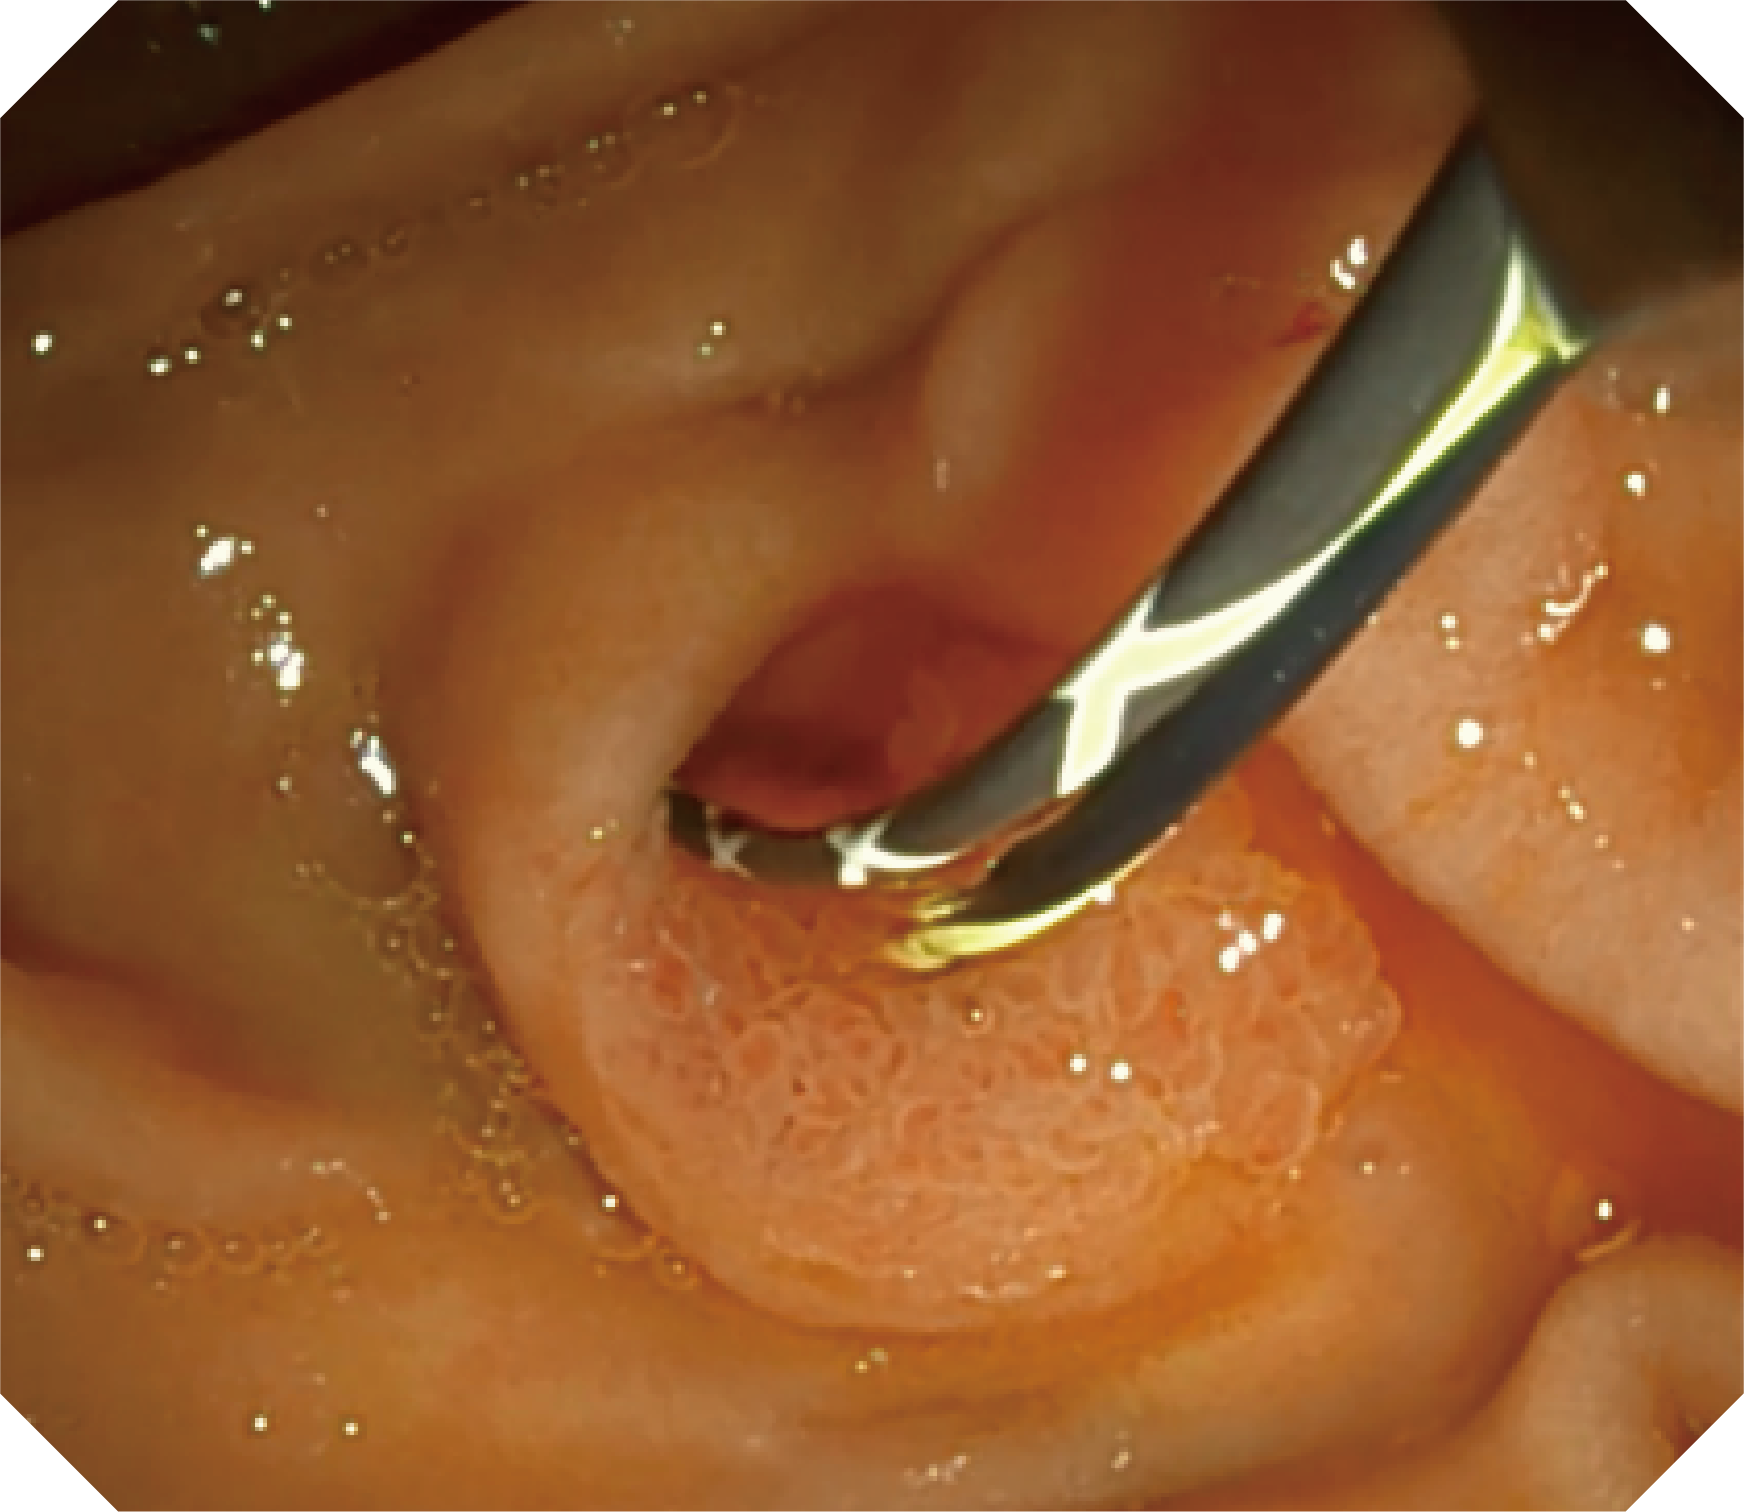

4.2mm大钳道,器械交换更顺畅

V槽设计提升导丝控制

优异的手术器械抬举性